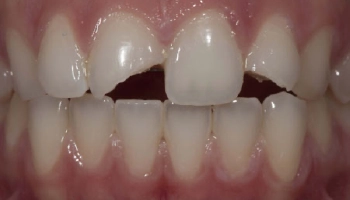

Trauma: Reattach Fragment with Composite Bonding

Before and after images of tooth fragment reattachment with composite bonding. Dental restoration showing composite bonding after trauma repair.